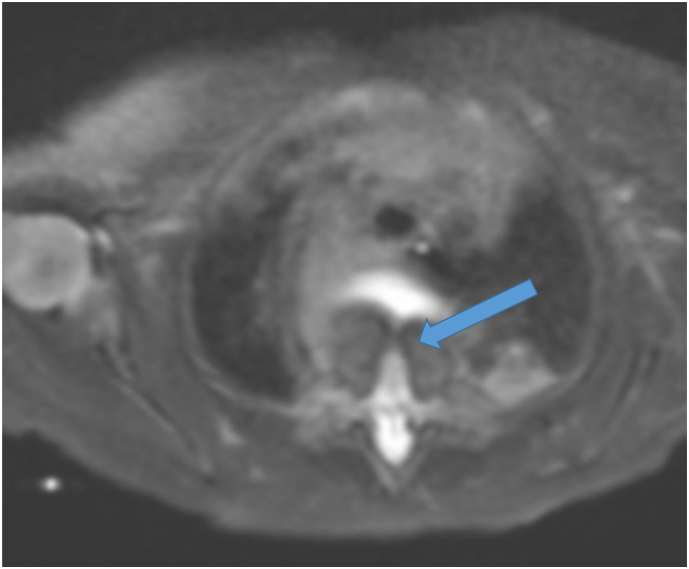

Neonatal MRI of the chest and spine showed a large posterior thoracic cyst measuring 6.6 × 4.2 × 5.7 cm suggestive of a foregut duplication cyst, with associated vertebral body anomalies (Fig. 4) involving the lower cervical and upper thoracic vertebrae. A small spinal syrinx was seen, with concern for spinal cord tethering.

Fig. 4.

T2 Weighted image on neonatal MRI demonstrating a vertebral body defect (arrow).